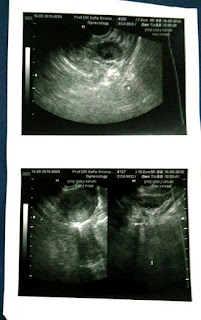

Pemeriksaan di kunjungan saya pertama kalinya ini, Dokter Sofie melakukan pemeriksaan USG TRANSVAGINAL. Suami pun diizinkan menyaksikan langsung pemeriksaannya sekaligus mendengar penjelasan dari Dokter Sofie.

Setelah saya dan suami dijelaskan pembacaan dari gambar USG tersebut, disimpulkan bahwa saya menderita PCOS.

Padahal istilah yang tepat adalah banyaknya folikel telur ( ukuran 4 - 8mm ) yang tidak berkembang yang tampak pada indung telur sebagai “ kista kecil-kecil ”.

BUKAN kista yang berukuran besar yang menunjukkan adanya tumor indung telur.

· Gambaran ovarium polikistik dari pemeriksaan USG.

1). Rahim / uterus saya : Normal (alhamdulillah)

2). Tidak ada kanker ataupun kista (alhamdulillahirabil'alamin)